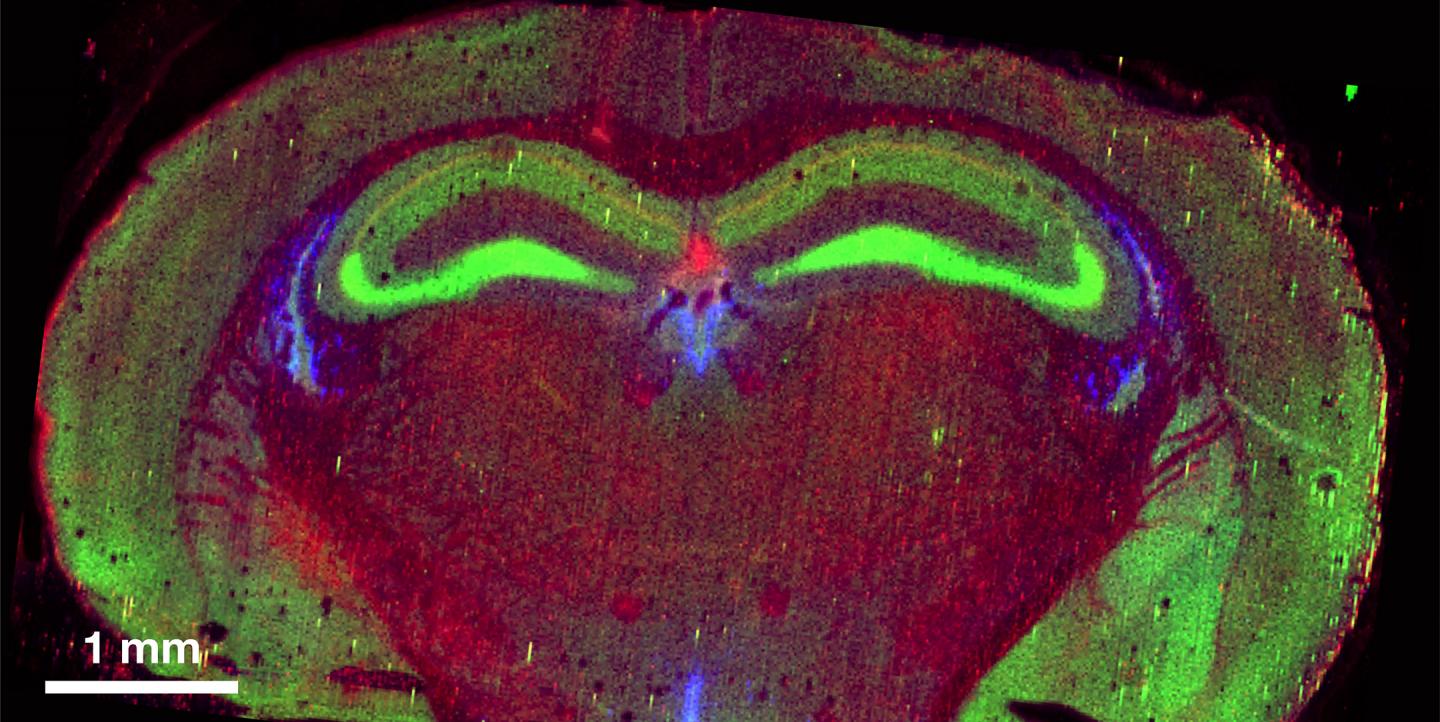

"The ability to map metals and metal dynamics in the brain opens important new avenues in neuroscience research, for neurodevelopmental and neurodegenerative diseases but also for the fundamental understanding of how neurons communicate," said Yevgenia Kozorovitskiy, assistant professor of neurobiology at Northwestern.

"The field has focused on calcium signaling in neurons for a long time, but zinc and other metals serve critical synaptic signaling roles in neurons that remain poorly understood in addition to their functions as co-factors for important neuronal proteins," she said.

A new mass spectrometry tool operated by QBIC will enable rapid 2D and 3D imaging of cells in tissue slices. Advances will include development of a completely integrated system with real-time multi-element imaging capabilities, standardized procedures for handling cryogenically preserved biological tissues and a universal cryo sample mounting system that can move between several different technologies that map and analyze elemental distributions.

The resource will also employ large sample format Scanning X-ray Fluorescence Microscopy (SXFM) utilizing one of the nation's brightest synchrotron radiation sources: the Advanced Photon Source, a U.S. Department of Energy Office of Science user facility located at Argonne National Laboratory. The SXFM will provide researchers with organ-wide information on metal distribution.